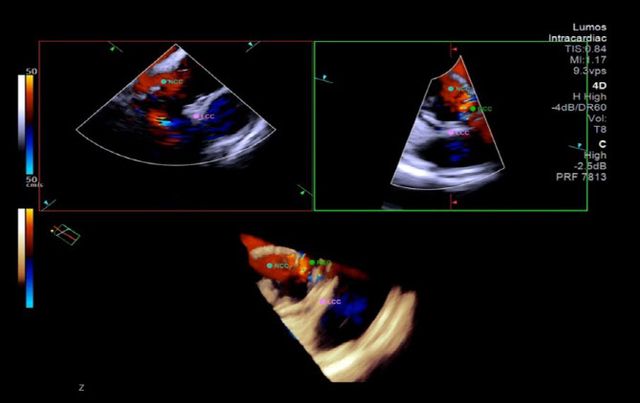

4D 심장내 초음파는 심장 내부의 구조를 실시간으로 정밀하게 보여주는 고해상도 영상 기술로, 기존 2D 심장내 초음파에 비해 다양한 각도에서 더 정확한 해부학적 정보를 입체영상으로 제공한다. 심장내 초음파 분야의 최고 권위자인 임홍의 교수는 “입체적 영상을 실시간으로 활용하면 시술자는 심장과 시술 장치의 구조를 보다 정확하게 파악할 수 있어, 시술의 효율성과 안전성을 최대로 높일 수 있다”며 “특히 정밀한 기술이 요구되는 경피적 대동맥판막 삽입술과 같은 고난도 시술에서 그 활용도가 더욱 기대된다”고 밝혔다